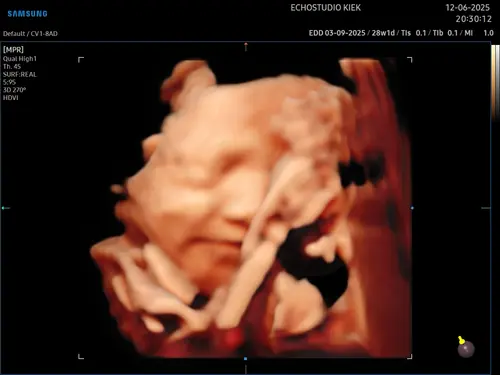

Dit was de echo van ons ventje... al met 22 weken gedaan toen ik in Nederland was. Vandaag 27 weken alweer.